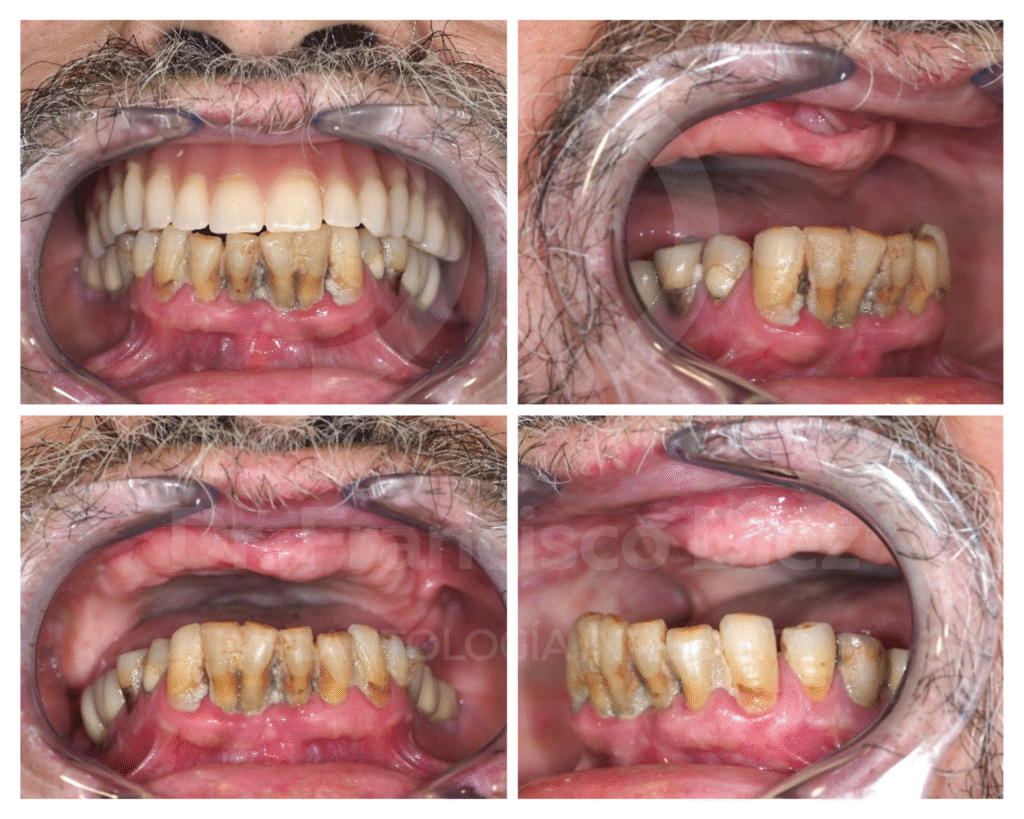

Varón de 74 años, fumador, edéntulo en la arcada superior y edéntulo parcial en la arcada inferior con periodontitis generalizada y periimplantitis de los 4 implantes que tiene. Con anterioridad se le han realizado diversas operaciones de regeneración ósea y elevaciones de seno maxilar, habiendo fracasado todas. Porta una prótesis completa superior inestable por la falta de reborde alveolar y la clase III escretal.

Radiográficamente se observa una atrofia severa de todo el maxilar superior, con pérdida del hueso total a nivel del seno maxilar derecho, probablemente por el fracaso de las intervenciones en el pasado, y áreas de apenas 1 mm de hueso en la zona antero superior. En el segundo cuadrante se observan restos de material, probablemente xenoinjerto, de los intentos de elevación sinusal en este lado. En la arcada inferior, se observa pérdida ósea generalizada, y acentuada a nivel del implante correspondiente al diente 46.